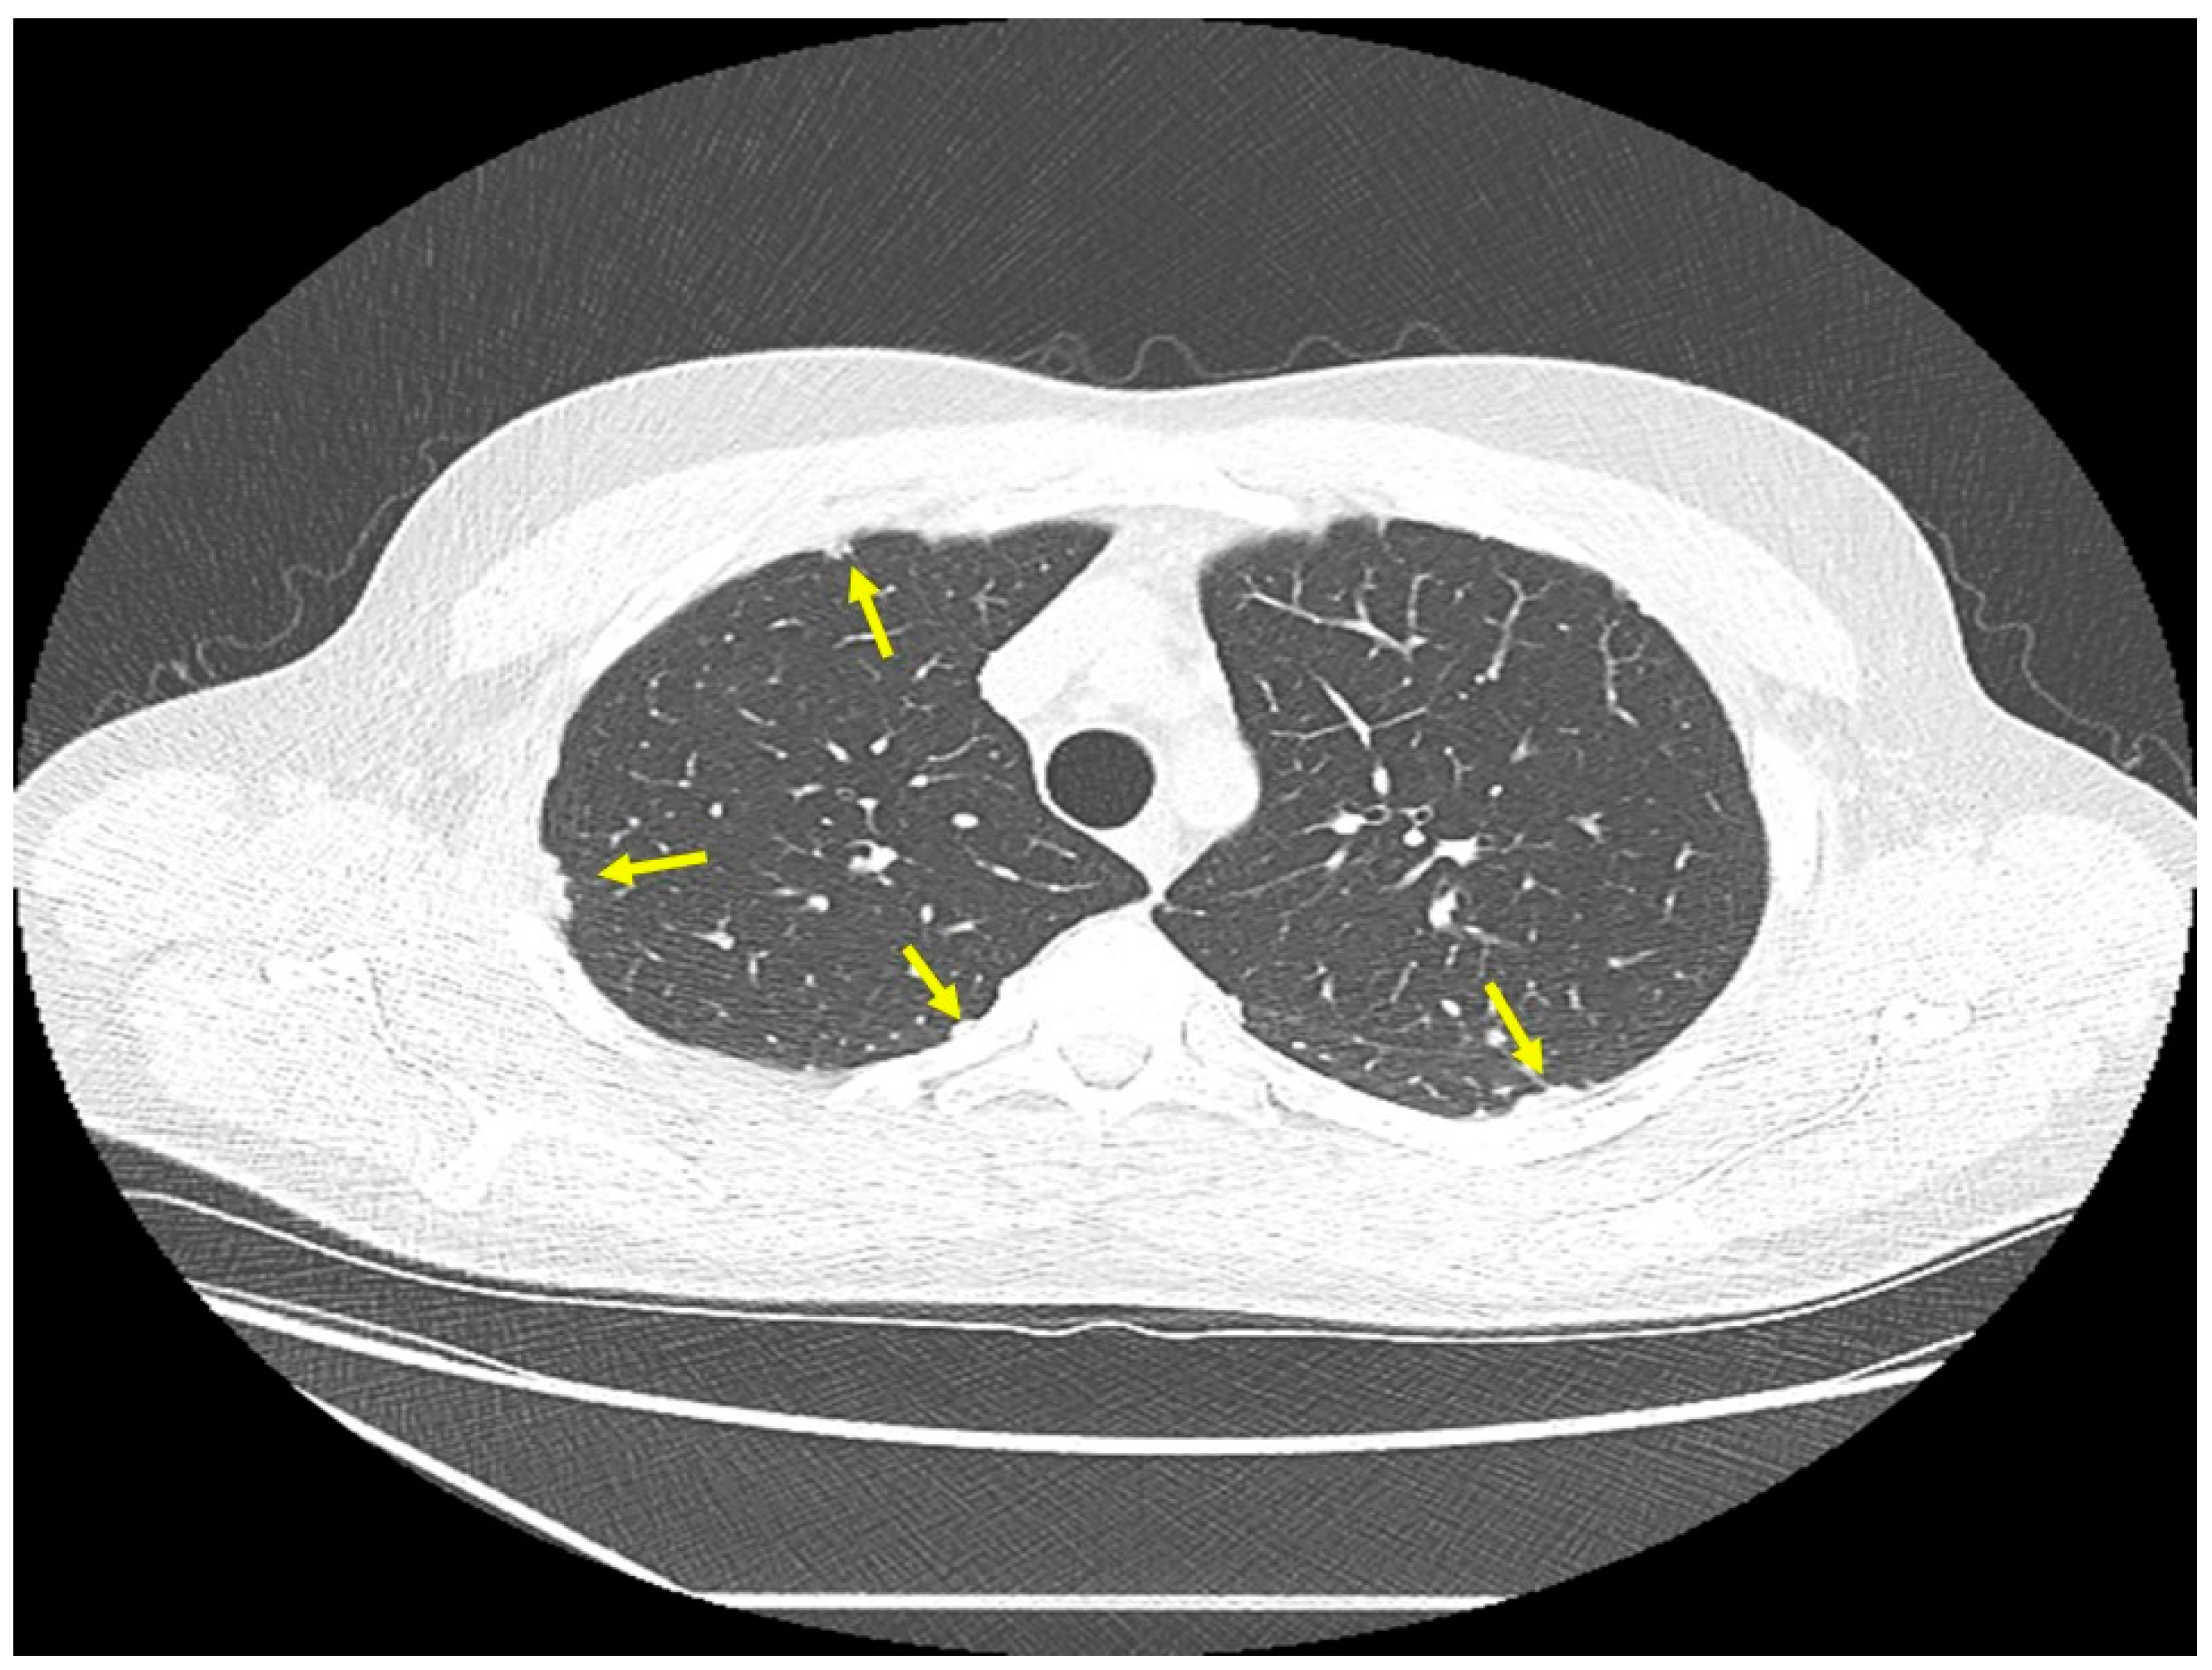

Figure 4.

Chest CT image of a patient with pulmonary sarcoidosis, demonstrating subpleural opacities from granulomatous inflammation (arrows).